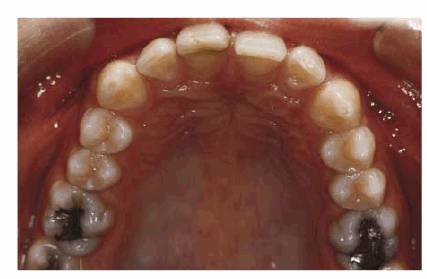

PROBLEM: This 21-year-old male model hesitated to smile because of his

diastemas (see Figures 23-14A, 23-14G, and 23-14I). The patient was also concerned about the appearance

into place. Figure 23-14E shows the occlusal view, indicating just how

much the left central incisor protruded before restoration. Four porcelain

laminates were used to create a symmetric arch with proper spacing (see Figure 23-14F). The improvement by the final result can be

Figure 23-14E: This before occlusal view shows how much the left central incisor protruded prior to treatment.

Figure 23-14F: Only four porcelain laminate veneers were necessary to eliminate the dark spaces between his teeth. Also note that the protrusion was eliminated.